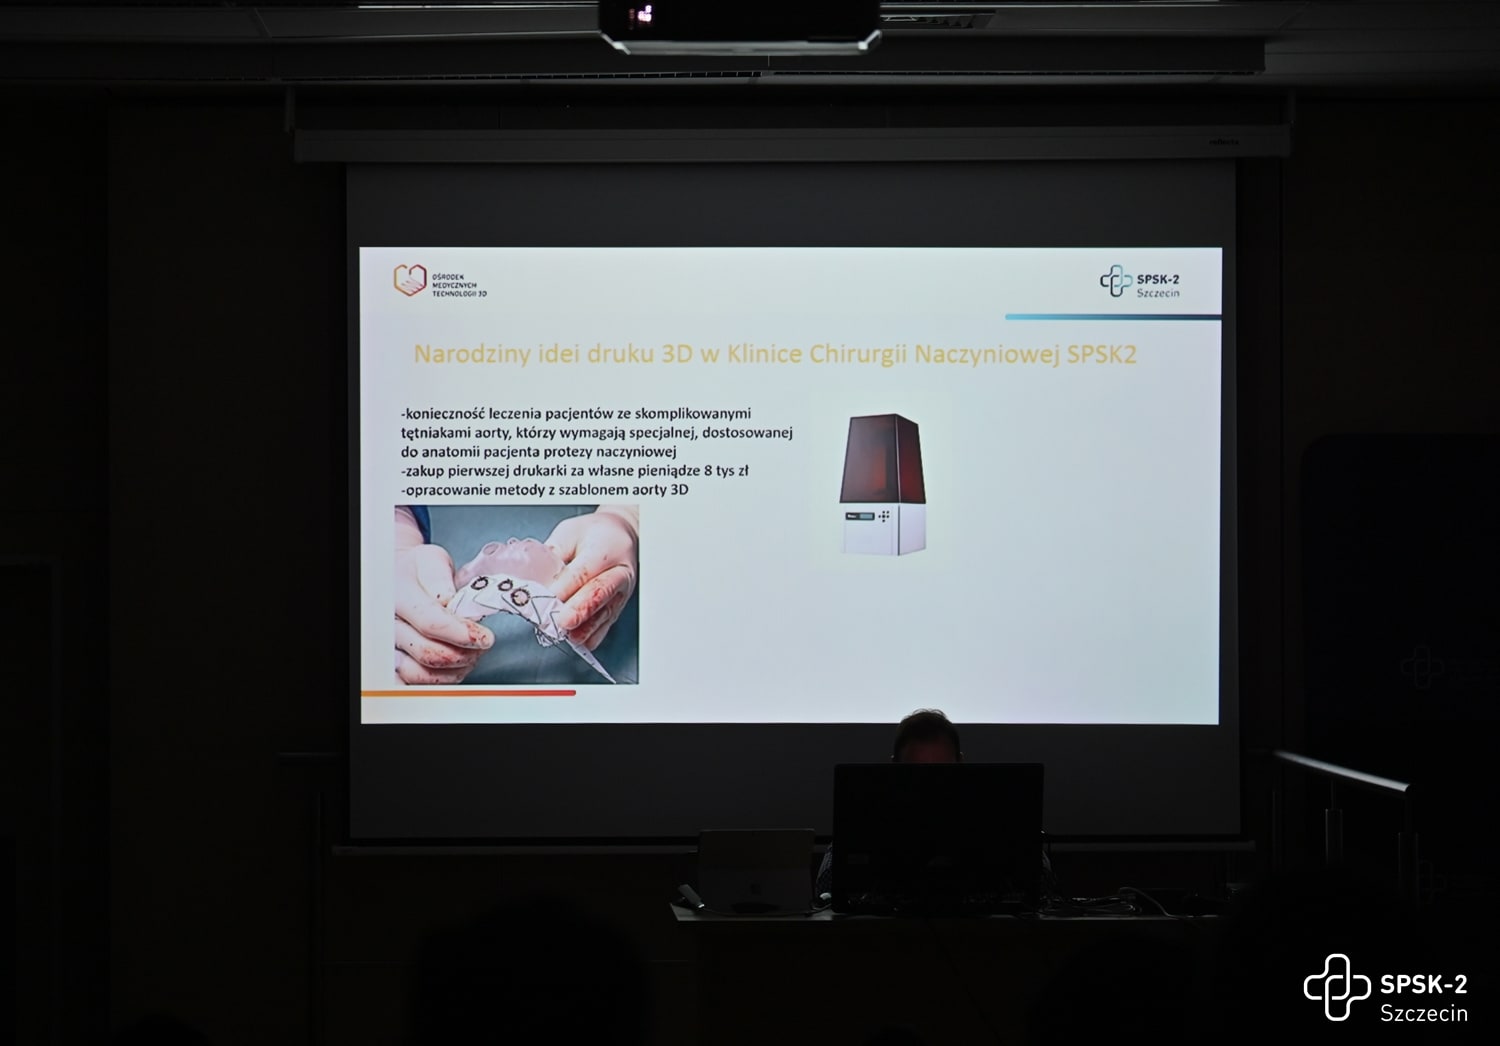

2022-11-07Lekarze Kliniki Chirurgii Naczyniowej, Ogólnej i Angiologii naszego szpitala dokonali pierwszego w kraju, całkowicie przezskórnego wszczepienia modyfikowanego stent-graftu. Była to operacja ratująca życie, a pomocna przy tym - technika druku 3D.

Dostępy całkowicie przezskórne (bez cięcia skóry) wykonuje tylko kilka ośrodków w Polsce i jest to metoda coraz częściej preferowana, ale głównie do mniej skomplikowanych przypadków. Tym razem do szpitala na Pomorzanach trafił 75-letni pacjent z objawowym tętniakiem okołotrzewnym (aorty piersiowo-brzusznej) - bolesnym, grożącym pęknięciem, a zatem stanowiącym zagrożenie życia. Dodatkowo chory nie miał szans na skorzystanie ze standardowego stent-graftu branchowego (z doszywanymi „rękawkami” na naczynia) czy fenestrowanego (z wyciętymi „okienkami” na naczynia) zamawianego u producenta z powodu występujących u niego dodatkowych naczyń, odchodzących od aorty (osobne ujście tętnicy wątrobowej). Nie mógł też czekać na wyprodukowanie stent-graftu szytego dla niego na miarę, bo trwałoby to 8-12 tygodni, a bolesność tętnika świadczyła, że rychło pęknie. Groziło to śmiercią pacjenta.

Leczenie stent-graftami modyfikowanymi jest w domeną naszych lekarzy Kliniki Chirurgii Naczyniowej, Ogólnej i Angiologii, którzy wypracowali wysokiej jakości standard postępowania w użyciu tej metody. Wykorzystując model aorty danego pacjenta, wydrukowany techniką 3D, modyfikują własnoręcznie, już na sali operacyjnej standardowe stent-grafty i dopasowują je indywidualnie do anatomii operowanego pacjenta. Po co? Bo mimo ogólnej takiej samej budowy każdego z nas, układ naczyń krwionośnych, ich budowa, odległości między poszczególnymi naczyniami różnią się u każdego człowieka. Dlatego dla efektywności działania wszczepianego, standardowego stent-graftu – proteza ta powinna być dopasowana do budowy chorego. Chirurdzy naczyniowi USK-2 są jedynym zespołem w Polsce, który tego typu zabiegi wykonuje rutynowo, również w przypadkach nagłych. Jednak taki sposób leczenia, jak i wszelkie inne zaawansowane procedury aortalne, wymaga licznych, często trudnych dostępów naczyniowych (np. nacięć w pachwinach, rękach i klatce piersiowej) – tj. cięć i operowania „na otwarto”. Dla chirurga taka operacja jest łatwiejsza, bo pole operacyjne jest widoczne jak na dłoni. Ale dla pacjenta dochodzenia do formy po takiej operacji jest długotrwałe, bolesne i mało komfortowe. Dlatego użycie przez szczecińskich lekarzy wyłącznie dostępu przezskórnego (bez cięcia) w leczeniu tętnika jest dużym krokiem na przód w chirurgii naczyniowej, a fakt, że to pierwszy tego typu zabieg w Polsce to ogromny sukces naszych „naczyniowców” i świadczy o ich doskonałej technice operowania.

Jedyny w kraju Ośrodek Medycznych Technologii 3D otwarty!

2022-10-13Po kilku latach wyczekiwania 7 października 2022 roku odbyła się uroczystość formalnego rozpoczęcia działalności nowoczesnego Ośrodka Medycznych Technologii 3D. To jedyna taka w Polsce, pierwsza, niepowtarzalna jednostka, która łączy zaawansowane technologie druku 3D, gogle mieszanej rzeczywistości i medycynę! Korzystać z tego będą mogły wszystkie dziedziny medycyny, nie tylko szczecińskich, czy polskich szpitali.

Pomysłodawcą powstania ośrodka jest dr n. med. Paweł Rynio – młody lekarz, chirurg naczyniowy, który rozwinął ideę w ramach programu Interreg VA, w którym partnerem naszego szpitala jest Uniwersytet Medyczny w Greifswaldzie. Jak mówił podczas uroczystości otwarcia Ośrodka przedstawiciel partnera - prof. Maciej Patrzyk – „Trzeci wymiar obrazu diagnostycznego pacjenta to było coś, czego brakowało lekarzom w medycynie. Płaskie obrazy nie oddają rzeczywistości na tyle dokładnie. Kiedy zobaczyłem w telewizji, że zespół prof. Gutowskiego w szpitalu w Szczecinie wykorzystuje druk 3D i gogle mieszanej rzeczywistości, wiedziałem, że tego szukam. Kiedy więc dr Rynio zadzwonił do mnie, to razu przystałem na współpracę”